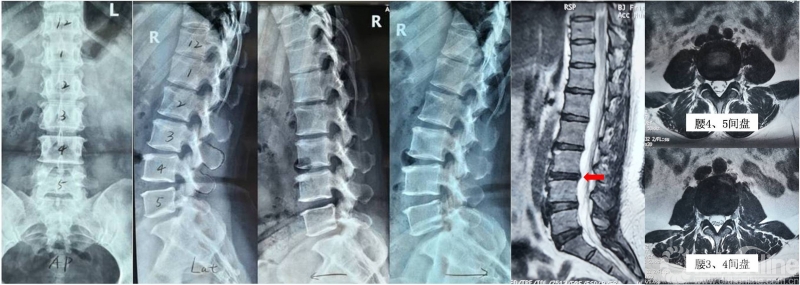

患者为41岁女性,主因“腰痛1年余,加重伴左下肢不适1月余”入院。1年前无明显诱因出现腰部疼痛,部位在腰背部及双侧腰骶部。半年前患者觉腰骶部疼痛明显加重,并出现左侧臀部及左大腿外侧酸胀不适感,前屈位、体位变动及站立时腰痛明显加重,卧床或腰部后伸时腰腿痛症状可部分缓解,步行100米左右即在腰痛基础上出现左侧臀部及左大腿外侧酸胀及麻木不适。保守治疗症状无明显改善,严重影响正常生活,腰痛及下肢疼痛VAS评分均达7分。查体无神经损害的定位体征。腰椎影像学检查可见多节段椎间盘退变性改变,以腰3/4为重,呈“黑间盘”及HIZ表现。未见明显椎管狭窄及神经压迫表现。综合患者腰腿痛的部位、疼痛特点以及影像学表现,我们高度怀疑为椎间盘源性腰痛。但对于椎间盘源性腰痛的诊断,更多是基于对症状特点的主观分析,有没有更为客观、敏感、准确的判断方法?一旦诊断为椎间盘源性腰痛,如何选择合理的治疗手段?针对上述问题,我们在术前进行了深入的讨论。

图1:术前X线提示腰椎轻度退变,动力位未见腰椎不稳表现;腰椎MRI提示腰3/4节段呈“黑间盘”,并可见HIZ表现(箭头所示)